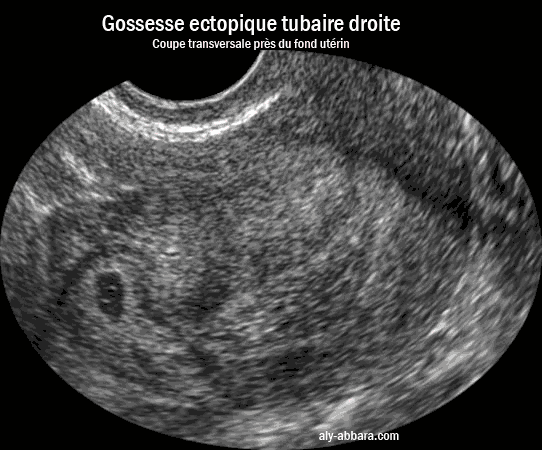

Grossesse extra-utérine dans la portion interstitielle de la trompe

(grossesse ectopique angulaire)

Il s'agissait d'une grossesse ectopique se manifestant par des métrorragies, mais sans aucune douleur avec un dosage de hCG plasmatique, 5000 UI/litre)

Grossesse extra-utérine dans la portion tubaire interstitielle droite